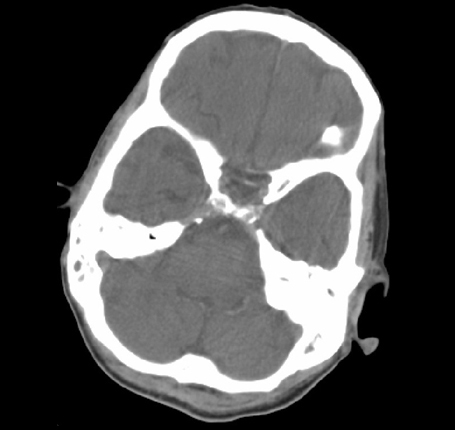

Menu Head and Neck Radiology CT Cranial Vault

• Falx Cerebri

• Hypophyseal Fossa